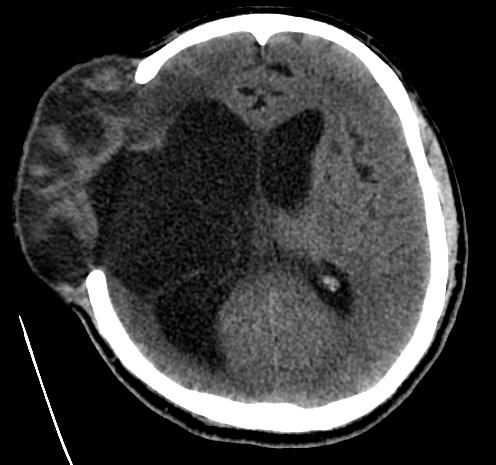

患者术前脑膨出情况及CT、MRI:

脑出血尤其是合并脑室出血的患者,由于血细胞崩解后使脑室壁产生纤维素样改变,同时含铁血黄色沉积导致脑脊液回流障碍,容易形成脑积水。脑积水的发生又进一步使病人变得反应迟钝、尿失禁、行走不稳等,严重影响脑出血术后患者的生活质量。脑穿通畸形合并脑膨出使脑皮层缺血软化坏死。进行颅骨修补术可以保持颅骨及颅腔的完整性,而严重的脑膨出给颅骨修补术带来了严峻的挑战。